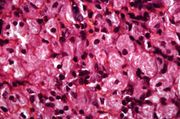

| 15:12, 20 August 2013 | IPLab5Gaucher8.jpg (file) | 53 KB | This is a higher-power photomicrograph of the spleen from this case. At this higher power individual cells can be better appreciated and the fibrillar nature of the eosinophilic cytoplasmic material can be seen. | 1 | |